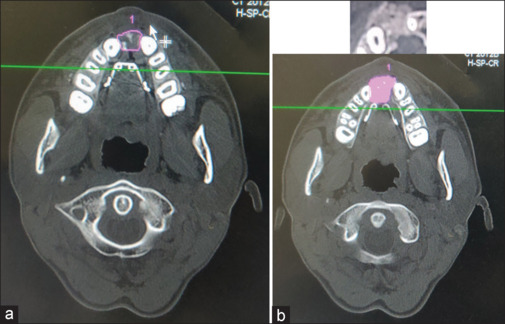

Materials and methods: A prospective study on patients with cleft alveolus, requiring bone grafting and reporting to our unit from October 2018 to October 2020 was included in this study. Group 1 (bone marrow aspirate with PRF along with cancellous iliac bone graft) and Group 2 (bone marrow aspirate concentrate and cancellous Iliac bone graft without PRF). Computerized tomography (CT) scan was done to assess the volume of defect at the following intervals: Pre-op, immediate post-op, and 12 months. The outcome is assessed using a CT scan by statistical analysis.

Results: Mean cleft alveolus volume measured preoperatively in group 1 was 2.5cc, post-operatively measured immediately was 3.2cc, and 12 months post-operative was 2.2cc. Mean volume defect in group 2 is 2.3cc, post-operatively measured immediately was 2.6 cc, and 12 months post-operative was 1.9cc. The average resorption rate at immediate post-op to 12 months interval in group 1 was 25% and in group 2 was 30%. The overall percentage of regenerated bone in group 1 was 75% whereas in group 2 it was 70%.